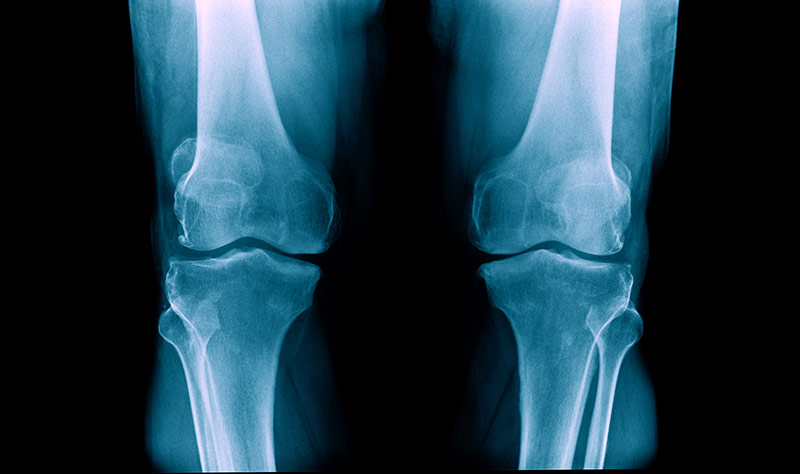

OA of the Knee

Understanding Knee Osteoarthritis (OA)

Knee osteoarthritis (OA) is a prevalent joint disorder characterized by the degeneration of the knee’s cartilage and underlying bone. It leads to pain, stiffness, and reduced joint function. Our clinical study in Phoenix is committed to shedding light on:

Symptoms of Knee Osteoarthritis (OA)